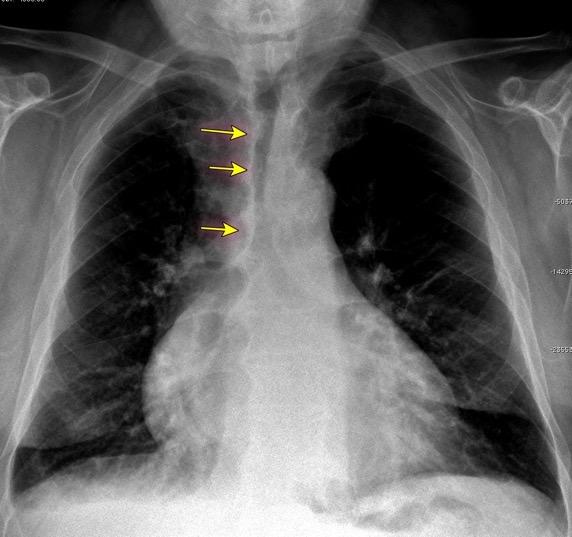

Triada de Garland

Ganglios paratraqueales derechos e hiliares bilaterales

95% de pacientes tienen ganglios hiliares bilaterales aislados o con afectación mediastínica (espec. paratraqueal derecho).

Criado E et al. Pulmonary sarcoidosis: typical and atypical manifestations at high-resolution CT with pathologic correlation. Radiographics. 2010